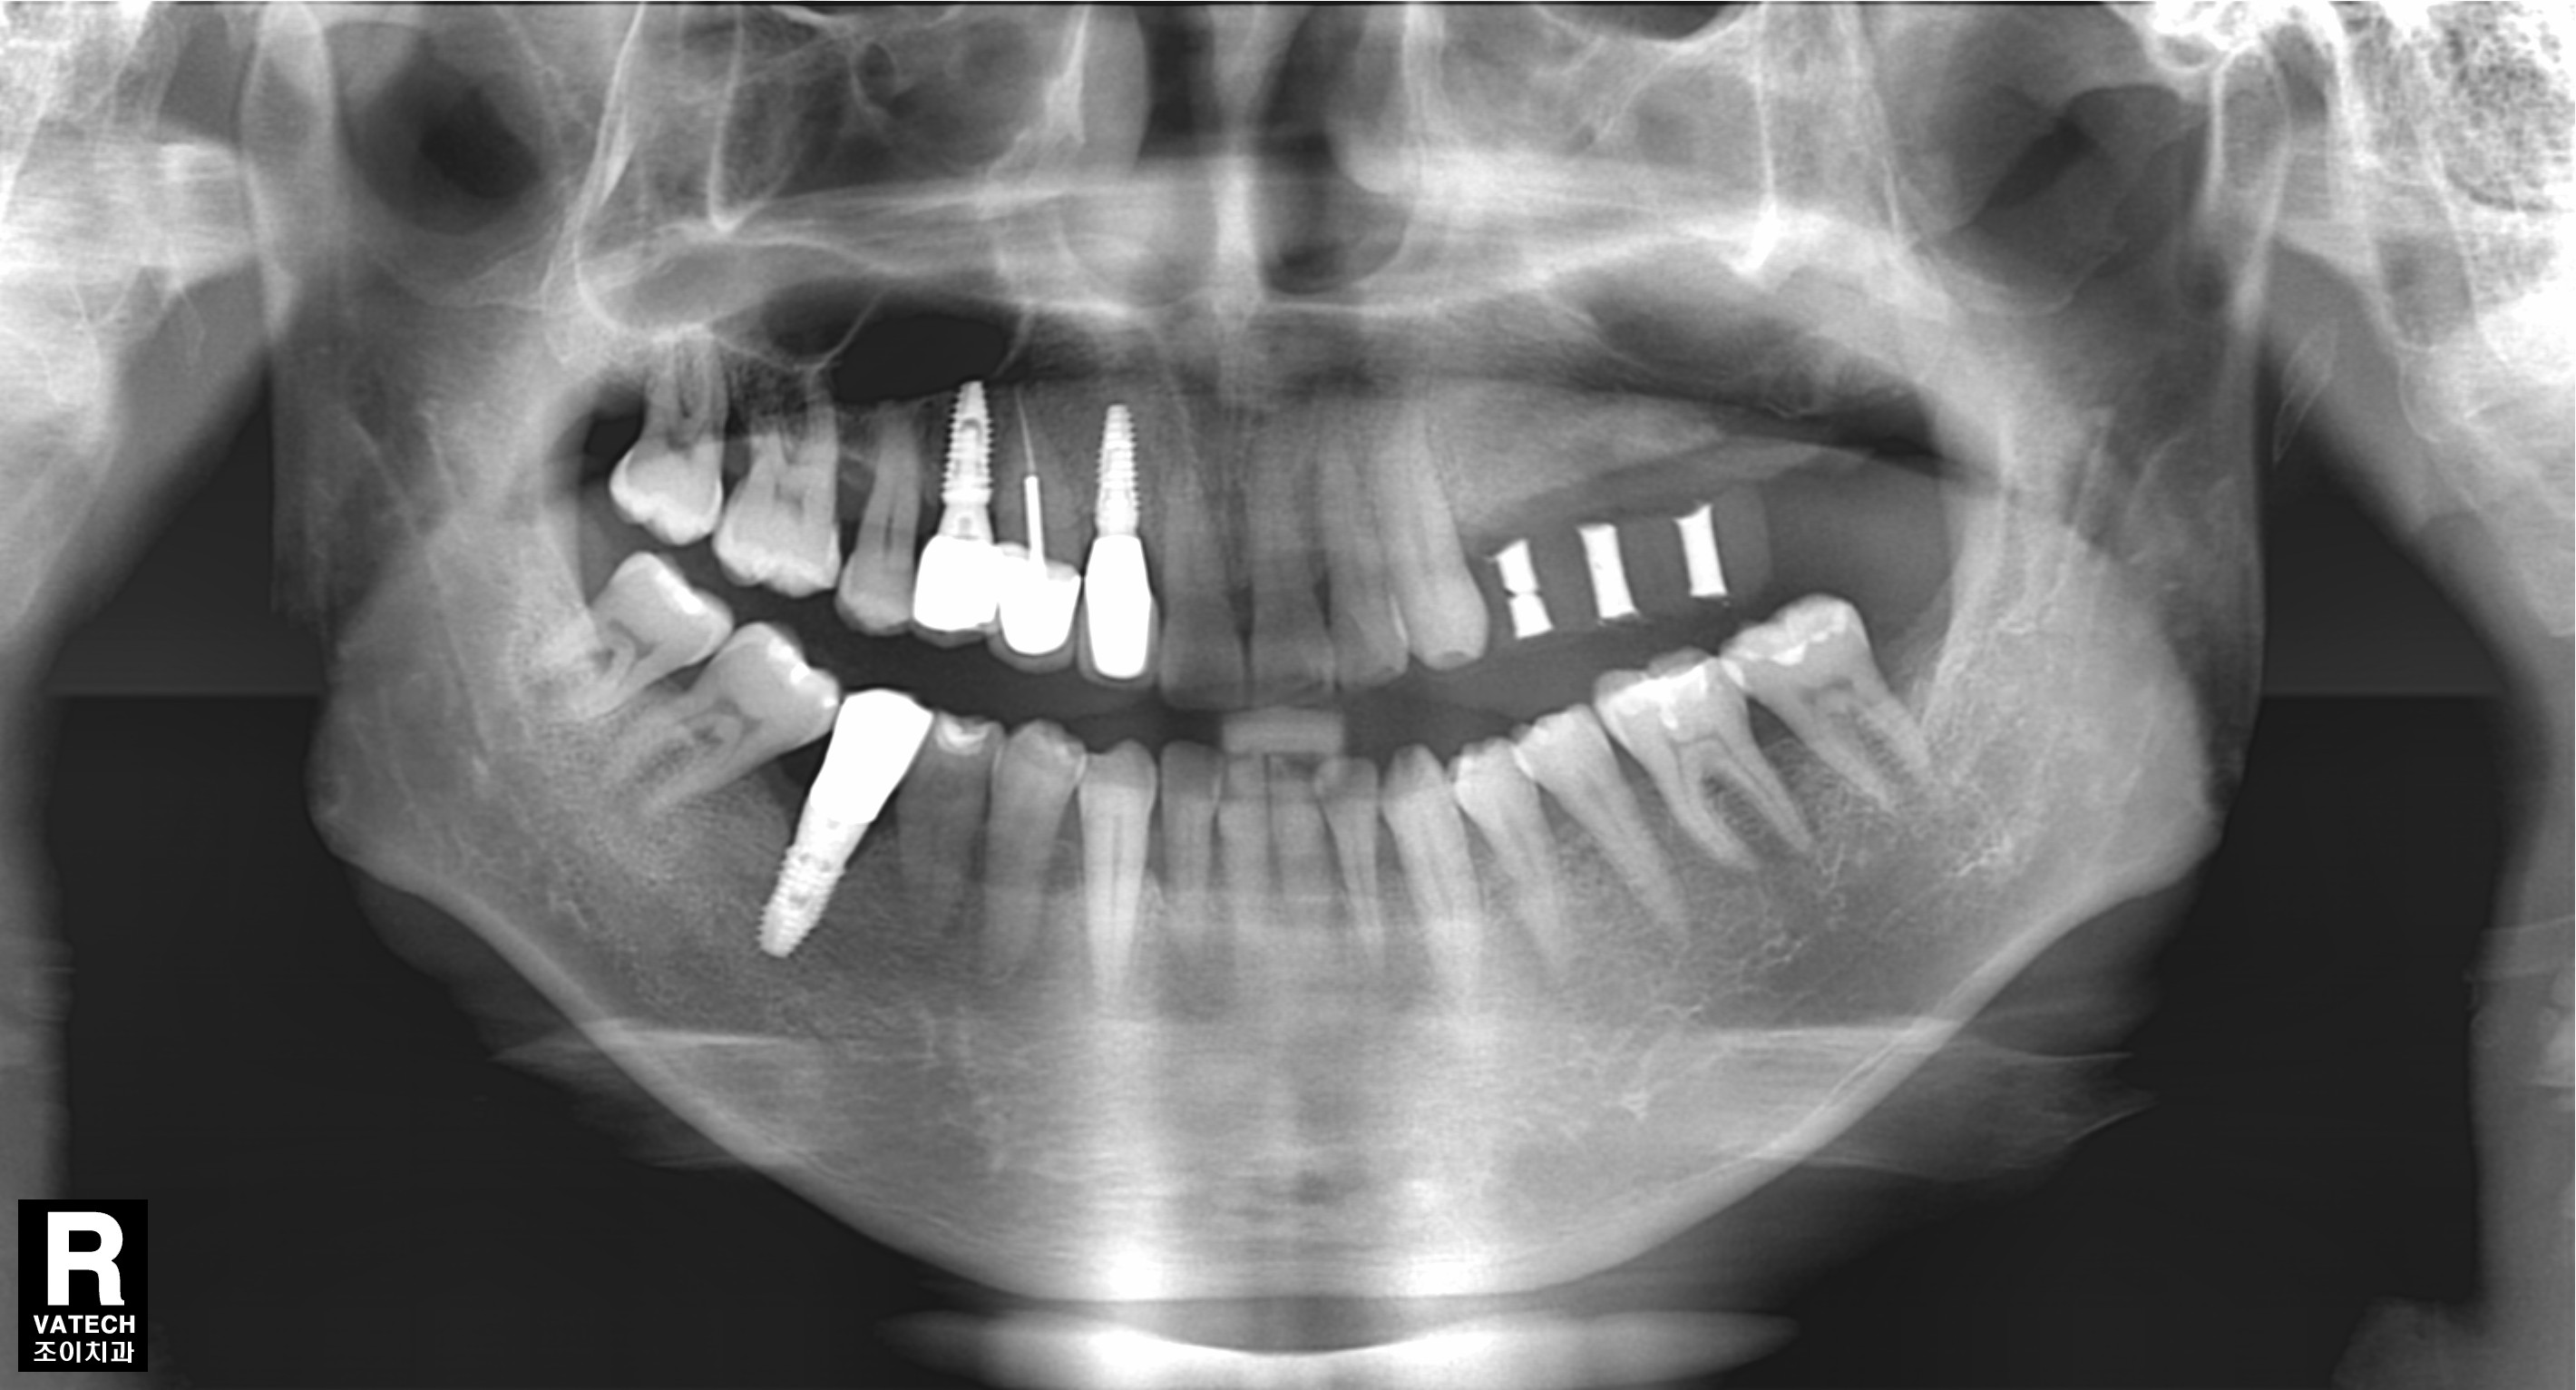

[임플란트] 제목 : 골이식

올바른 임플란트 식립의 초석은 충분한 뼈.